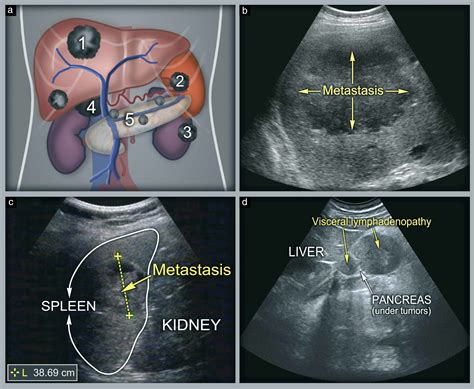

An ultrasound of abdomen is used to evaluate a wide range of conditions affecting the abdominal organs. Some of the most common uses include:

• Spleen: Checking the spleen for enlargement, cysts, or tumors.

• Kidneys: Examining the kidneys for stones, tumors, cysts, or other abnormalities.

The images obtained from an ultrasound of abdomen are reviewed by a radiologist, who provides a detailed report to the referring physician. The results can help diagnose various conditions, including:

• Pancreatic Disorders: Inflammation, tumors, and cysts in the pancreas can be identified.

• Kidney Stones: The location and size of kidney stones can be determined.